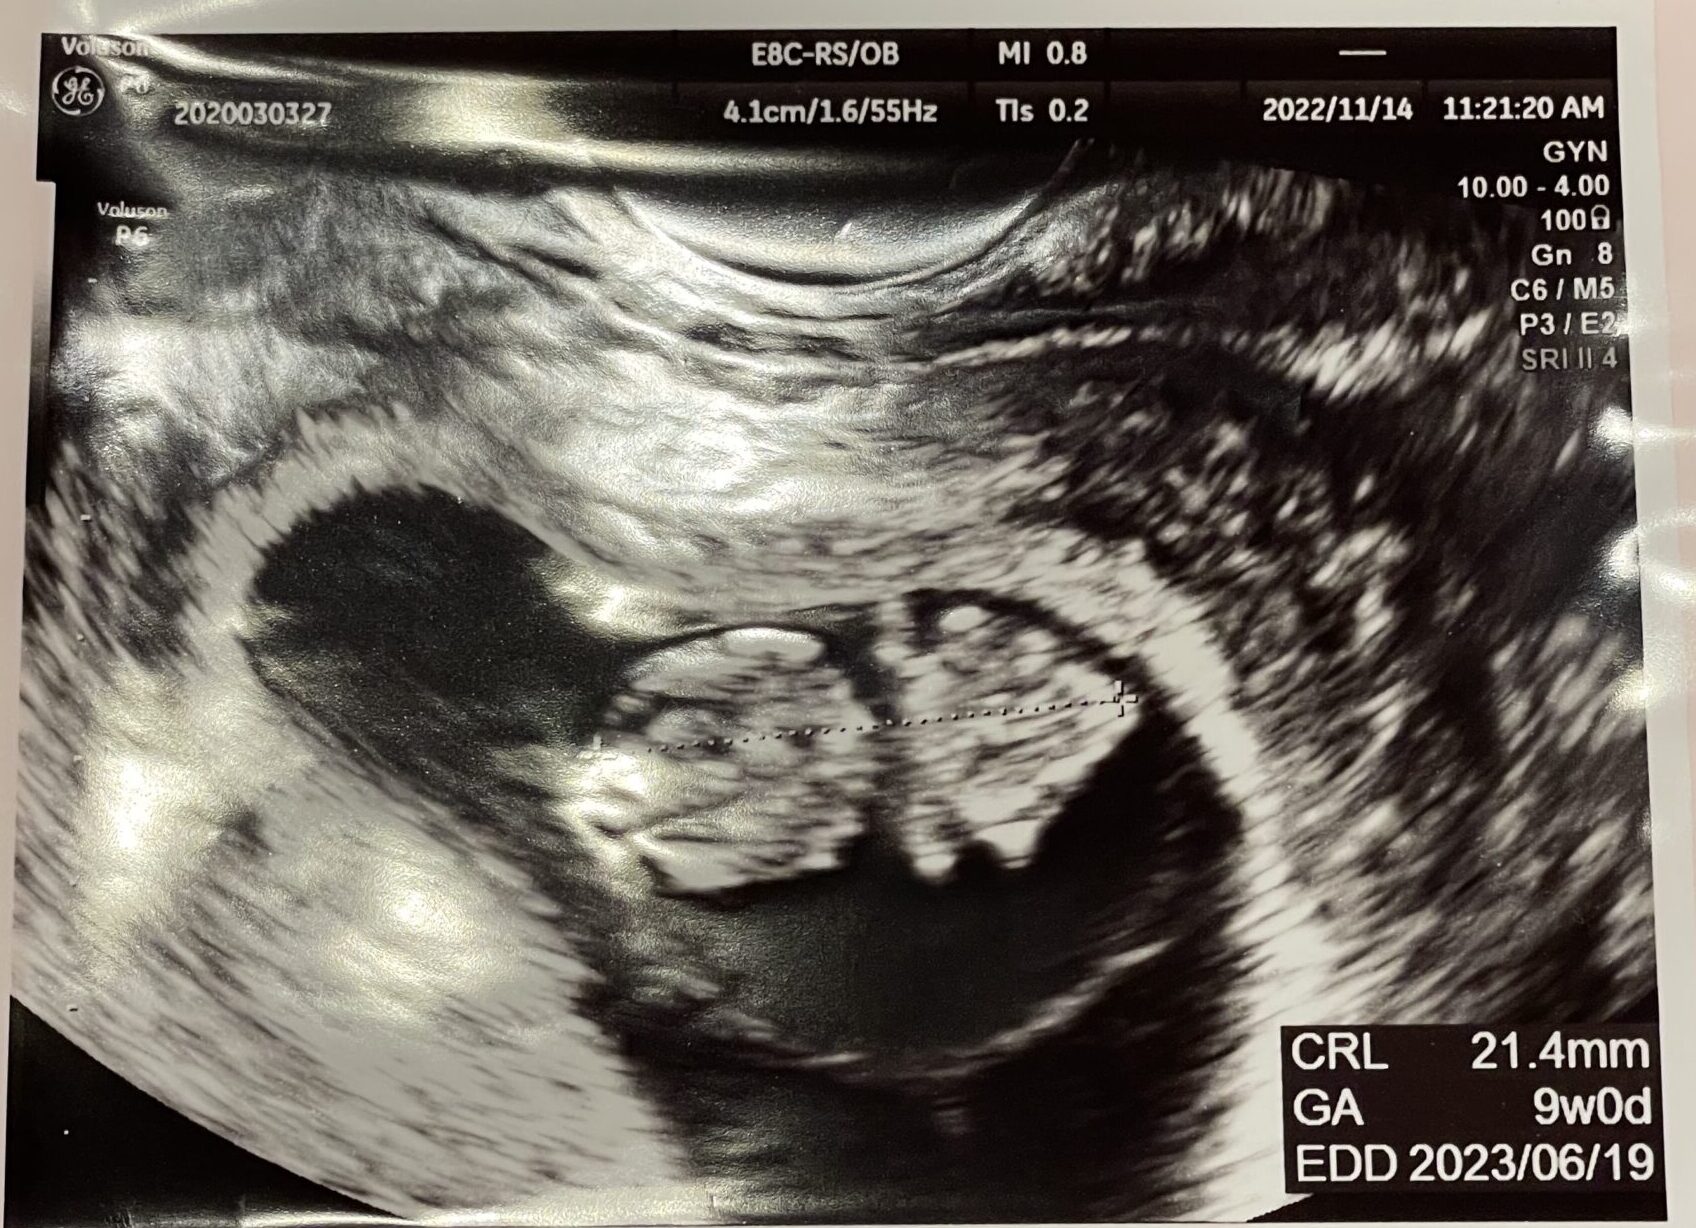

2022年11月中旬。

3回目の通院・2回目の妊婦健診に行きました。赤ちゃんはちゃんとお腹にまだ居てくれていました…!

エコー写真では、かわいいクリオネちゃんがちょっと大きくなっていて、とても安心しました^^

- 経膣エコー(内診)

経膣エコー

何度やっても身体がこわばってしまう経膣エコーですが、かわいい赤ちゃんの姿が見られてほっと安心する瞬間でもありました。